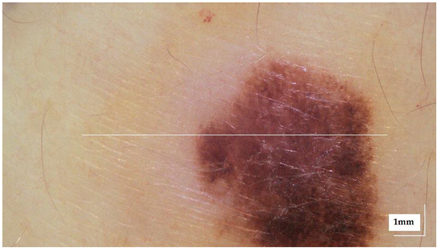

Appendix A. Selected Cases Studies’ HE Histopathological Images (Limited to OCT FOV)

| Superficial spreading melanoma (SSM) Case 2 | Localization: right forefoot (right ankle) |

![]() | ![]() |